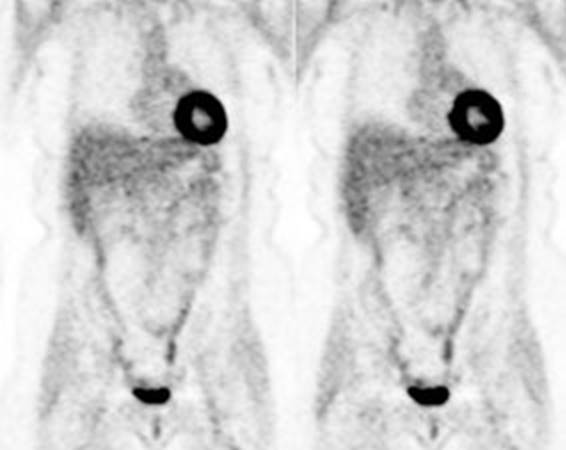

Figure 26 - Normal

vascular activity: Faint

activity can be seen in the descending thoracic aorta (black arrows)

Figure 27 - Normal

breast activity: Faint

activity can normally be seen in the breasts (black arrows)